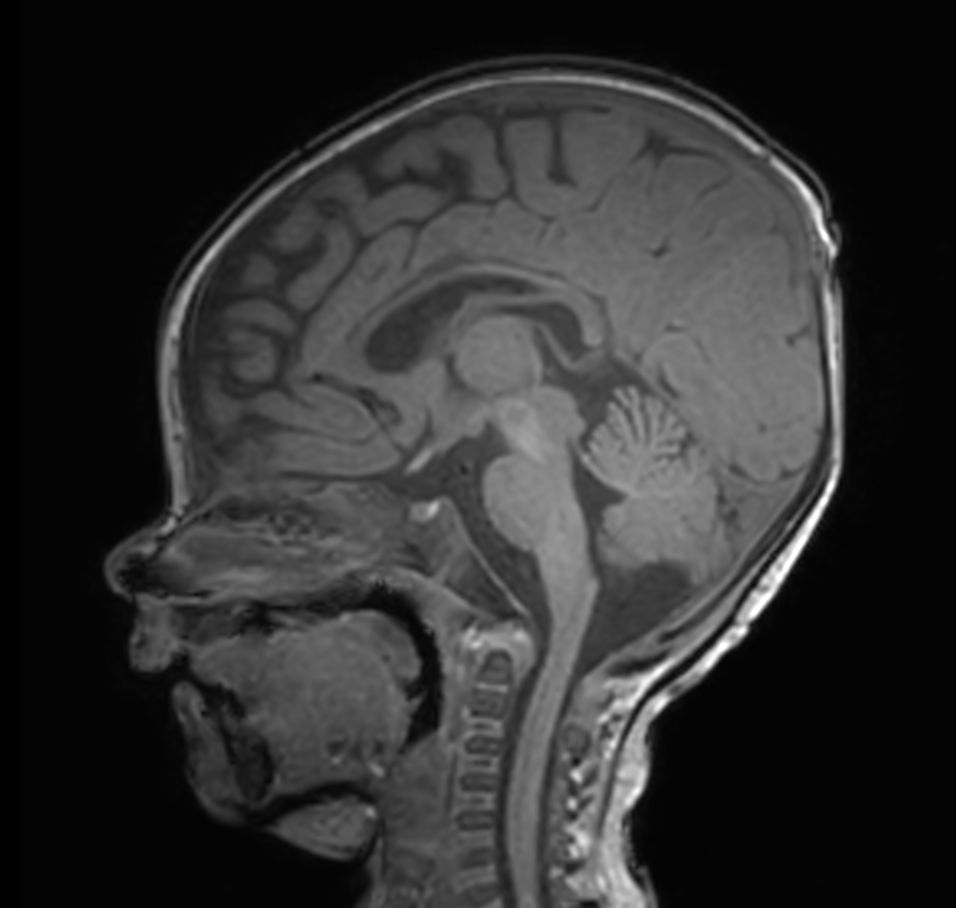

Sagittal 3D T1w TFE with ComforTone